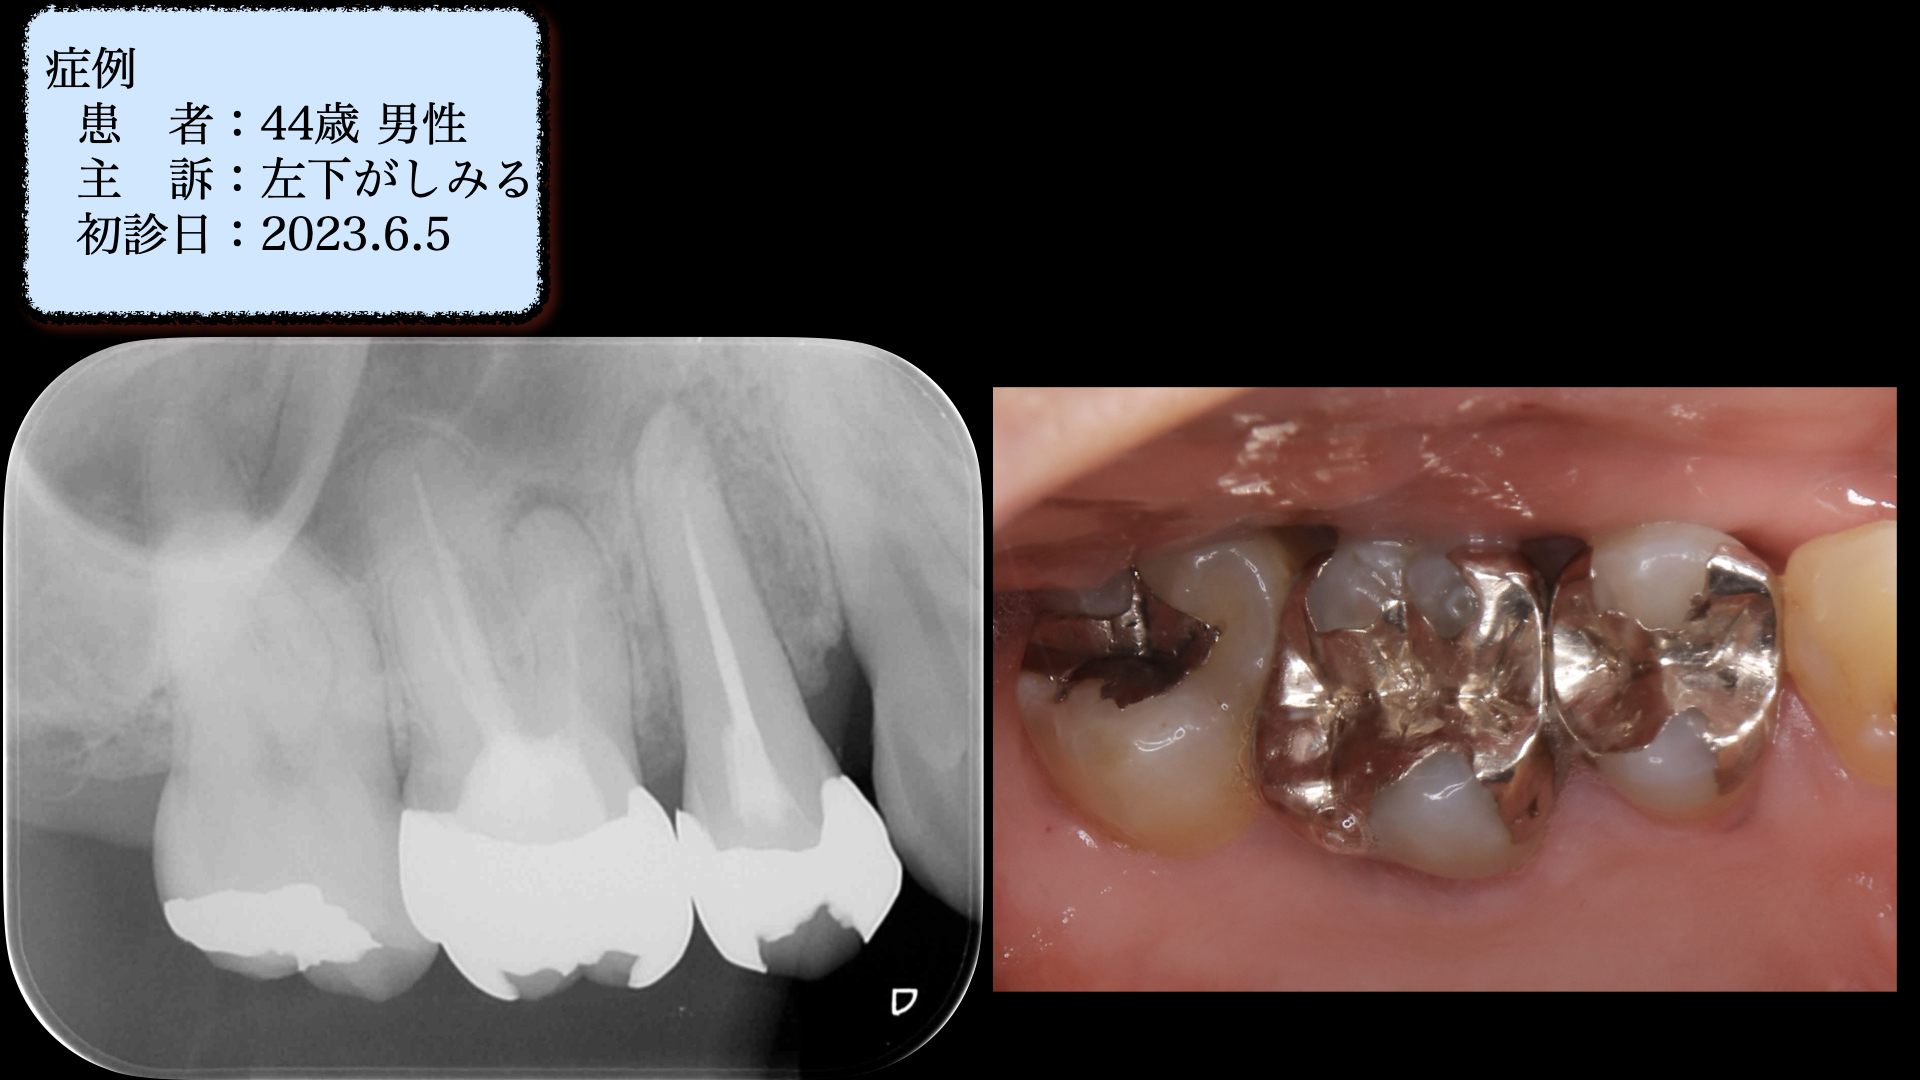

Before